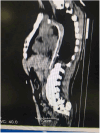

Infections associated with healthcare manipulations, particularly bloodstream infections stemming from catheters and medical devices, significantly heighten the probability of vertebral osteomyelitis. The diagnosis of infective endocarditis (IE) frequently overlaps with vertebral osteomyelitis (VO). In cases where individuals are suspected of having hematogenous vertebral osteomyelitis and have an intravascular catheter or device, it is recommended to undertake blood culture collection. We present a case of a 39-year-old male with a history of interventional AVM embolization and cerebral angiography, experiencing recurrent vertebral osteomyelitis. No definitive source of infection had been found, and transthoracic echocardiography (TTE) yielded negative results for IE. In Trans Esophageal Echocardiography (TEE), a retained micro-catheter extending from the aortic arch to the inguinal artery was discovered. Although we cannot definitively attribute the source of the osteomyelitis to the retained micro-catheter, no episodes of infection have been reported ever since. This case underscores the need to enhance our approaches and guidelines related to operating protocols in the surgical setting. Improving these guidelines can prevent similar occurrences in the future, emphasizing the importance of continuous improvement in healthcare practices.